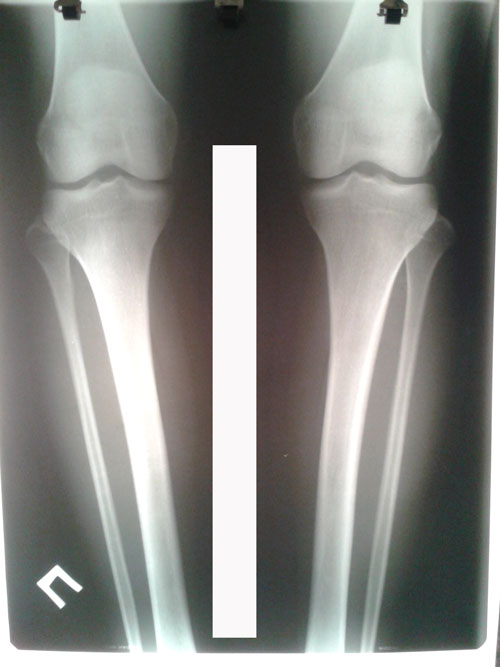

Рентген до операции.

20160709_130321.jpg